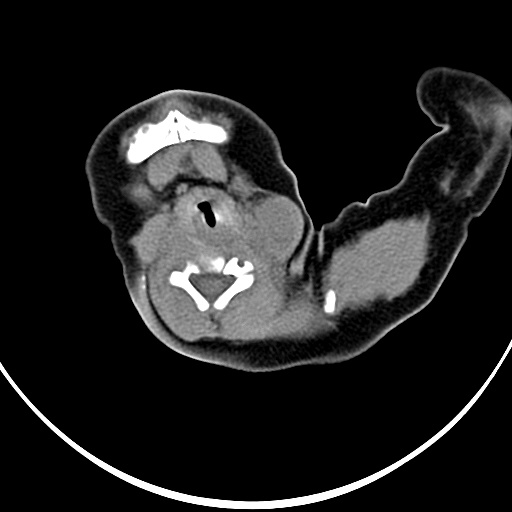

病灶与左侧胸锁乳突肌分界不清,软组织密度,不似囊性改变,从病人的年龄及病变性状首先要除外先天性斜颈(肌性斜颈)可能。

左侧胸锁乳突肌肿大,考虑产伤所致

胸锁乳突肌挛缩(斜颈)?